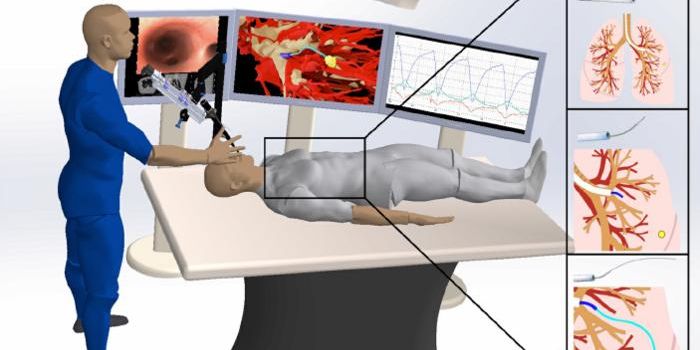

SEP 21, 2023TechnologyA recent study published in Science Robotics examines how a tiny robot can maneuver through lung tissue with the goal of ...